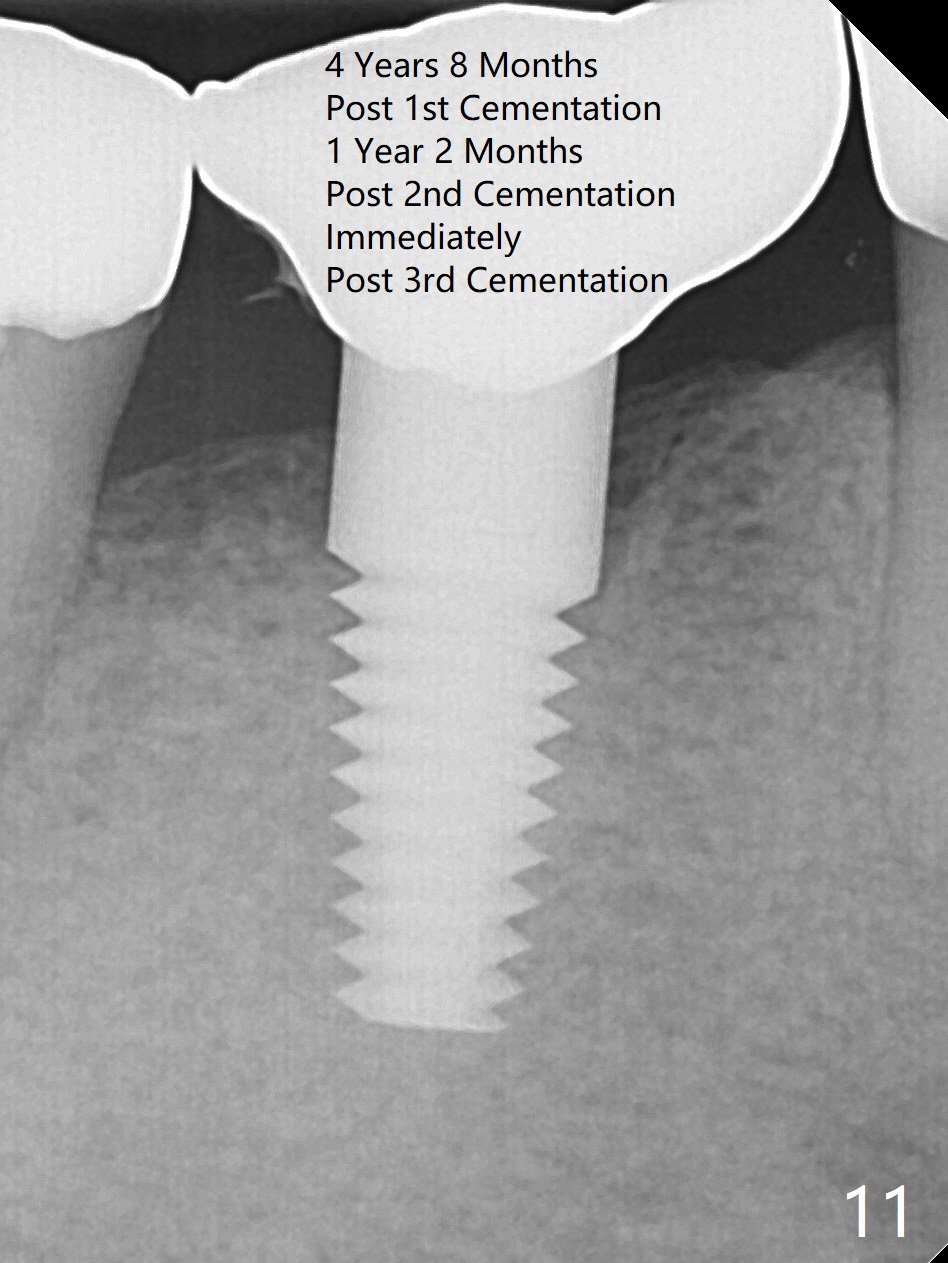

A 47-year-old man has history of bruxism, chipping porcelain from #29-31 FPD (Fig.1). Following sectioning the FPD, osteotomy is created (Fig.2: 5x14 mm drill) for placement of a 5x14 mm tissue-level implant (Fig.3,4). A 4x3 mm abutment (Fig.5 (lingual view) A) with 3 vertical slots (* for increased retention) is placed to retain periodontal dressing. The crown over the implant has dislodged 3 times over 28 months post cementation (Fig.6). It appears that the top of the abutment is too rounded. Clinical exam shows that the abutment height can be more, although the tooth #3 is supraerupted (Fig.7 (orthodontic intrusion is not indicated because of furca infection)).

Therefore a larger and longer abutment should be used (4.5x5 mm 0°). First of all, install Isolite. Remove cement from the access hole of the unipost with Cavitron. The cement was used to cement the crown. Use Tatum driver to remove the abutment. If it does not work, make a slot on the top of the abutment and use a regular screw driver to unscrew the abutment. Second, apply Cetacaine and perform laser gingivectomy to expose the implant margin. Temporary crown should be made to keep the margin and the space just created around the implant. Third try in the new abutment. Fourth reduce the abutment height carefully and make slopes corresponding the cusps of the opposing tooth. Reduce the opposing tooth if necessary. Last, consider Ketac cementation. Use resin bonding (with syringe tip) when an angled abutment is used. The bonding has higher retention than Ketac.

Pre-impression photos show supraerupted #3 (Fig.7). Clearance is a little more than 1 mm between the mesiopalatal cusp of #3 (Fig.7 *) and the rounded abutment (Fig.8). Removal of the abutment turns out to be easy. Reduction is confined to the opposing tooth (slopes of the cusps). No occlusal reduction is done for the new abutment as mentioned above except for 2 retention grooves. One-mm reduction ring barely passes the occlusal clearance (Fig.9). No cement is applied to the abutment in case a longer abutment may be required. Bone density seems to remain the same or increase after cementation of a new crown (Fig.7). The redo crown remains in place 1 year post cementation.